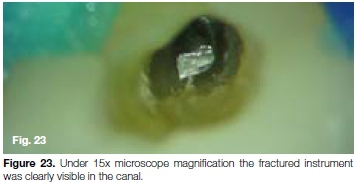

The patient, a 21 year old male presented with a fractured rotary file in his maxillary left upper central incisor. The fragment (14mm long) was located approximately 4mm apically from the cemento-enamel junction at the coronal aspect extending apically to about 5 mm from the apical foramen (Figure 22). Under 15x microscope magnification, the fractured instrument was clearly visible in the canal (Figure 23).

It was decided to use the Terauchi File Retrieval Kit (TFRFK) (Dental Cadre) to assist in removal of the fractured instrument. The 12 o'clock Micro-spoon ultrasonic tip (Figure 24) was used to penetrate through between the file and the canal wall in circular motion until it was noticed that the fractured file was loose in the canal. Considering the length of the fragment it was decided to attempt retrieval using the Yoshi Loop (Dental Cadre) (Figure 25a and 25b), a stainless steel micro-lasso that extends from the end of a stainless steel cannula attached to a handle with a retraction button for tightening the loop around the file segment.